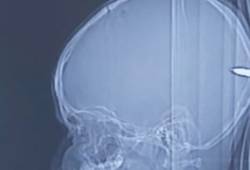

| Israeli Doctors Remove Mystery Bullet from Arab Boy’s Brain; Facebook Blocks Rabbi for Teaching Spiritual Aspect of Corona; Latest from Israel! |